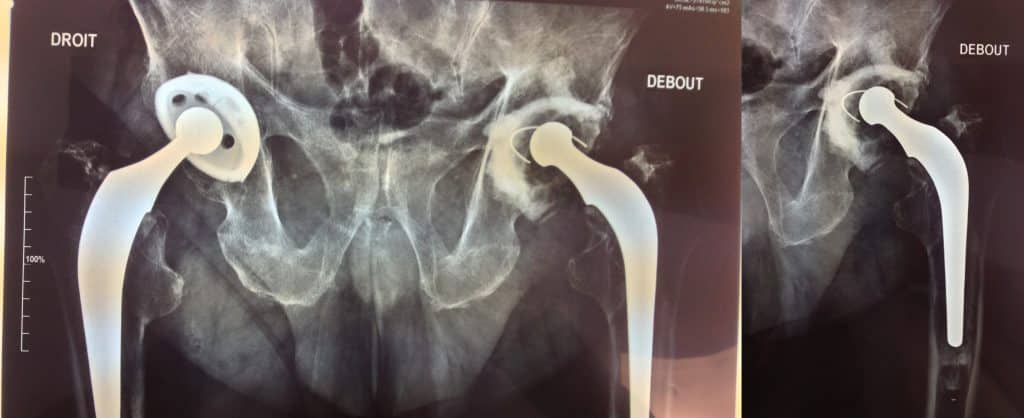

Effet “jumbo cup ” (56) , ascension et appui sur la corticale du toit du néocotyle.

Pivot fémoral Press Fit sans ciment.

Déambulation autorisée à J 2.

Suites simples avec retour à domicile.